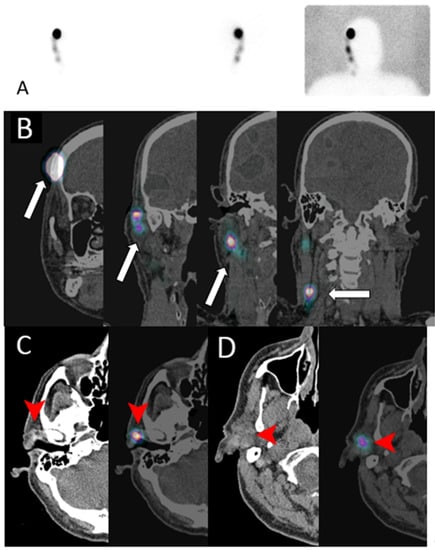

Lymphoscintigraphy

- Intenzo, C.M.; Truluck, C.A.; Kushen, M.C.; Kim, S.M.; Berger, A.; Kairys, J.C. Lymphoscintigraphy in Cutaneous Melanoma: An Updated Total Body Atlas of Sentinel Node Mapping. Radiographics 2009, 29, 1125–1135. [Google Scholar] [CrossRef] [PubMed]

- Uren, R.F.; Howman-Giles, R.; Chung, D.; Thompson, J.F. Imaging Sentinel Lymph Nodes. Cancer J. 2015, 21, 25–32. [Google Scholar] [CrossRef]

- Olmos, R.A.V.; Hoefnagel, C.A.; Nieweg, O.E.; Jansen, L.; Rutgers, E.J.; Borger, J.; Horenblas, S.; Kroon, B.B. Lymphoscintigraphy in oncology: A rediscovered challenge. Eur. J. Nucl. Med. Mol. Imaging 1999, 26 (Suppl. 4), S2–S10. [Google Scholar] [CrossRef]

- Skanjeti, A.; Dhomps, A.; Paschetta, C.; Tordo, J.; Bolton, R.C.D.; Giammarile, F. Lymphoscintigraphy for Sentinel Node Mapping in Head and Neck Cancer. Semin. Nucl. Med. 2021, 51, 39–49. [Google Scholar] [CrossRef]

- Quartuccio, N.; Garau, M.L.; Arnone, A.; Pappalardo, M.; Rubello, D.; Arnone, G.; Manca, G. Comparison of 99m TC-Labeled Colloid SPECT/CT and Planar Lymphoscintigraphy in Sentinel Lymph Node Detection in Patients with Melanoma: A Meta-Analysis. J. Clin. Med. 2020, 9, 1680. [Google Scholar] [CrossRef] [PubMed]

- Kwak, J.J.; Kesner, A.L.; Gleisner, A.; Jensen, A.; Friedman, C.; McCarter, M.D.; Koo, P.J.; Morgan, R.; Kounalakis, N. Utility of Quantitative SPECT/CT Lymphoscintigraphy in Guiding Sentinel Lymph Node Biopsy in Head and Neck Melanoma. Ann. Surg. Oncol. 2019, 27, 1432–1438. [Google Scholar] [CrossRef] [PubMed]